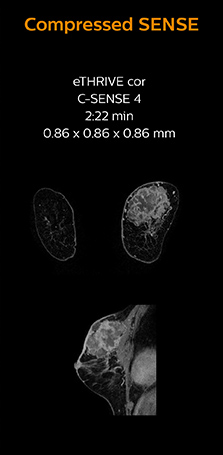

“In breast scanning, high resolution is important to help me identify very small mammary lesions, so, we need high spatial resolution in 2D T1- and T2-weighted images, as well as a short scan time. Compressed SENSE has allowed us to increase spatial resolution, which benefits our diagnostic confidence.”

Dr. Koyama says that he used to believe that high resolution MRI at 1.5T required long scan times, and SNR was low. “With Compressed SENSE, however, it is possible to acquire high quality images, even with higher Compressed SENSE factors, so in a quite short time.”

Dr. Koyama says that a C-SENSE factor of 4.0 was chosen to increase their spatial resolution in 3D dynamic breast scanning. “In addition to a high temporal resolution, we also require high spatial resolution, which helps us to see details of the internal structure of the lesion and to see lesions separately from normal anatomic structures. We can also see if a lesion extends into adjacent organs and anatomic structures.”

This patient underwent MRI on Ingenia 1.5T with Compressed SENSE. Compressed SENSE was used to reduce the scan time in order to decrease the time that the patient may experience discomfort and pain, both of which may lead to patient motion. The 3D BreastVIEW and 3D high resolution mDIXON images – both mDIXON contrasts are acquired in the same exam – show high quality images even with the shorter scan time. The spatial resolution of the dynamic scan with Compressed SENSE is higher than in the previous protocol (not shown) which allows for better visualization of the lesion with respect to the muscles of the thoracic wall and better delineation of small structures.

For breast imaging, a fast, high resolution scan can be important for a female patient having to lie in an uncomfortable, face-down position in the scanner. Compressed SENSE also helps us to obtain higher* quality images using 3D BreastVIEW and 3D high resolution mDIXON sequences in the same examination time as in our previous exam protocol.